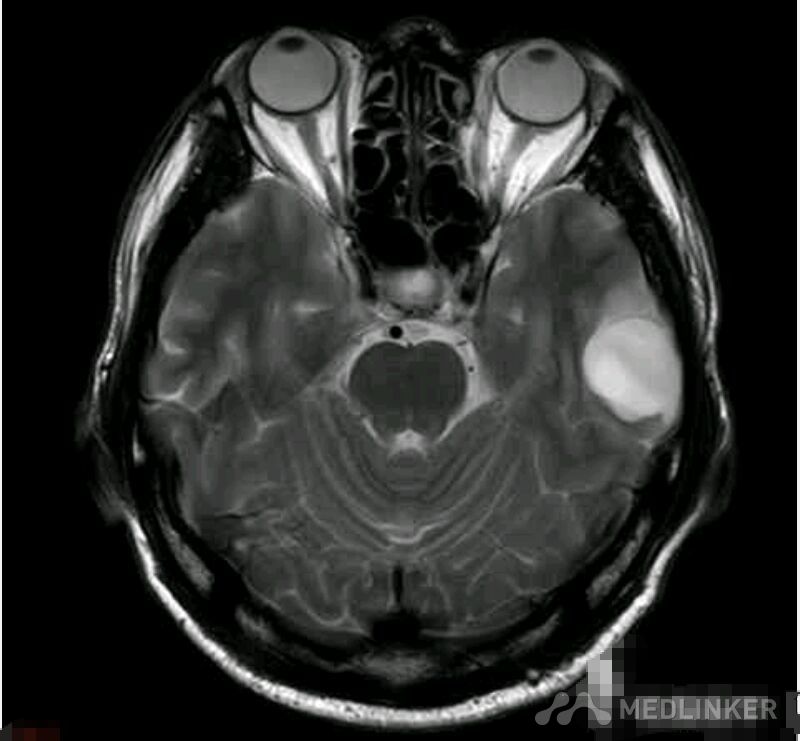

脑囊虫病高清影像资料分享

脑囊虫病经典资料